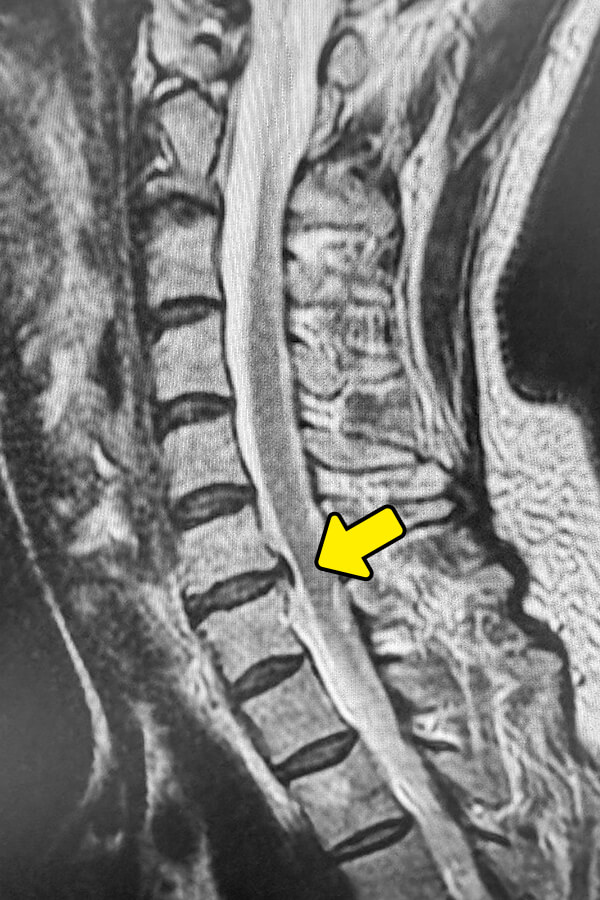

以前より首から両肩にかけての鈍痛が続いており、日常生活でもかなりのストレスを感じておられる方です。以前に腰に対して治療を行っていることから、頸椎治療を目的に来院されています。頸椎のMRI検査を行った所、C4/5・C5/6・C6/7の3箇所の椎間板でヘルニアを認めます。椎間板容量は減少傾向であり、一部50%程度まで低下している可能性があります。Annulargram検査を行った所、椎間板損傷部があり、造影剤が漏れ出すところが確認できました。ディスクシール治療の適応であると判断し治療しております。治療時間は18分程で、鎮静剤を使用しますので痛みも不安も感じられることはありませんでした。

頚椎の配列や骨の変形、不安定性を確認。ヘルニア自体はMRIで詳しく評価 - MRI検査

ヘルニアの位置、大きさ、形状、神経根や脊髄の圧迫状態を確認する最も重要な検査

MRI検査により、ヘルニアの有無だけでなく、どの神経がどの程度圧迫されているかを確認できます。ただし、画像所見と症状が必ずしも一致するとは限らないため、専門医による診察とあわせた判断が重要です。当院ではMRI画像で来院前に治療の可否が分かる無料画像相談を行っておりますので、是非ご利用ください。